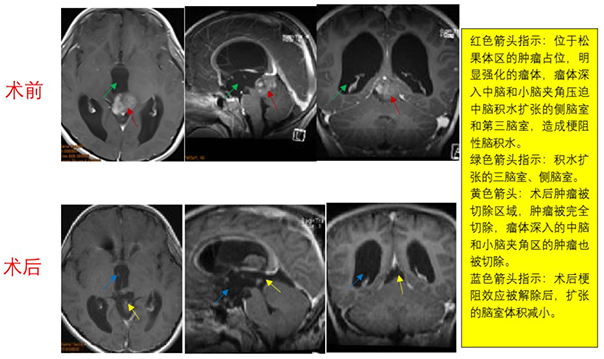

【松果体肿瘤】松果体区肿瘤能

松果体悬挂在大脑的正中央。18世纪法国科学家勒内笛卡尔认为松...